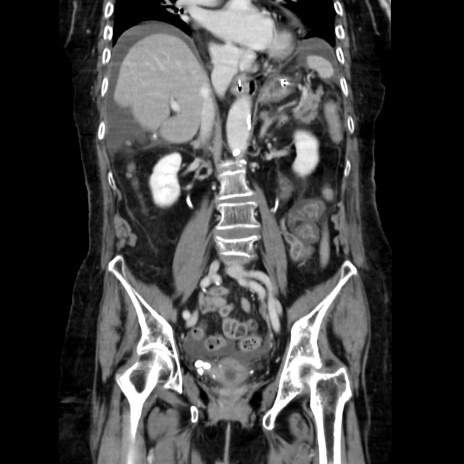

症例40(冠状断像)

冠状断像